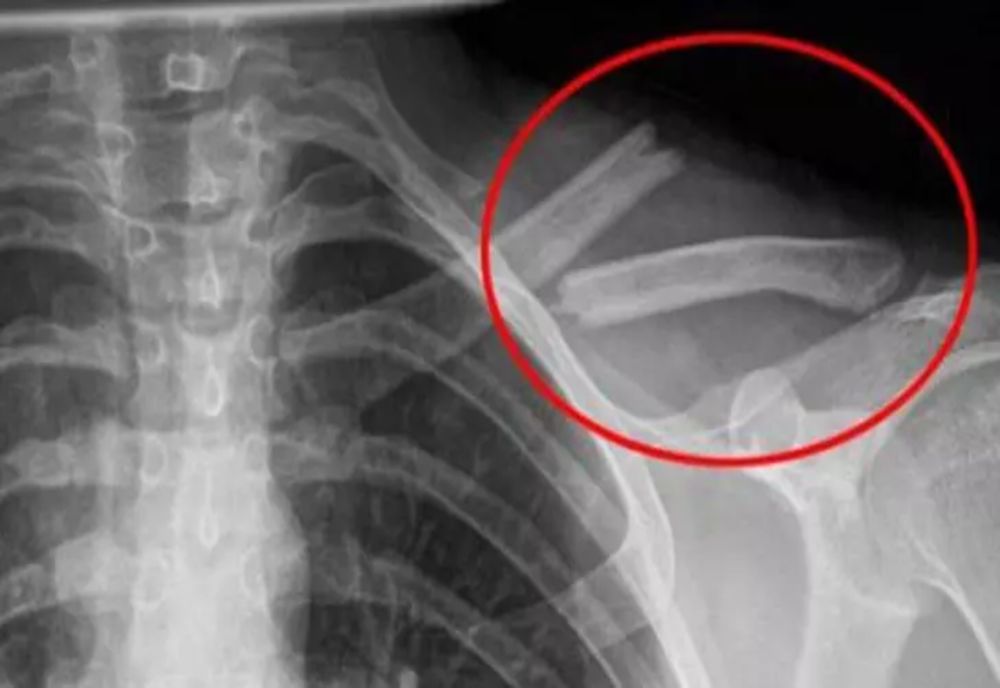

Consumul de băuturi acidulate duce la distrugerea oaselor pe termen lung.